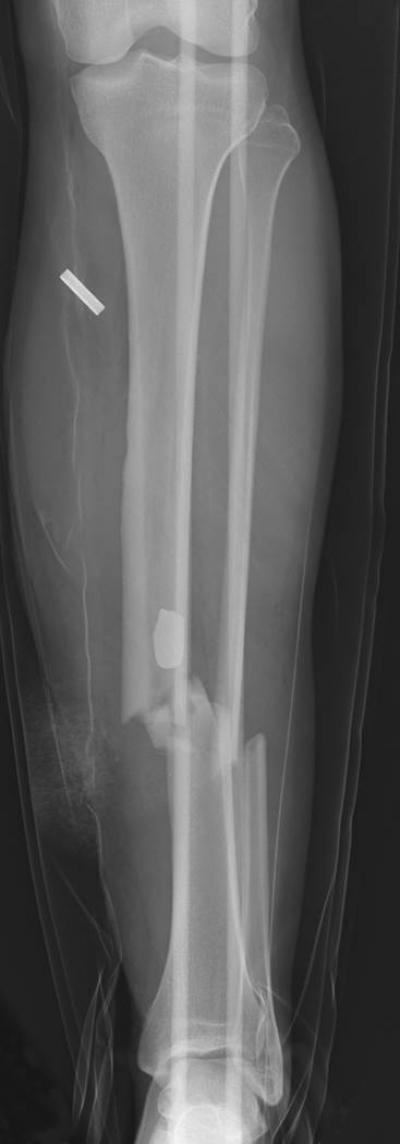

Victims from the Boston Marathon bombing were subject to blast waves and blast wind resulting in soft tissue damage (1), limb fractures (1), and amputations. The study demonstrates the systematic need to exam each extremity for musculoskeletal, neurological and vascular damage. In accordance with previous evidence, radiography (X-ray) and computed tomography (CT-scan) should be used liberally to detect foreign objects, to define basic penetration patterns, and assess bony and soft tissue injuries.

On April 15, 2013, at approximately 2:49 p.m. two pressure-cooker bombs exploded one after the other at the Boston Marathon finish line. As a result of the bombings, there were three fatalities and 264 casualties, with the most severe injuries involving lower extremities of those located closest to the blasts. Shrapnel disbursed by the bombs included pieces of metal, nails and ball bearings. Injuries resulting from the Marathon bombing are relevant to the fields of rheumatology, rehabilitation, orthopedics and musculoskeletal imaging.

"In an era of terrorism, even clinicians serving non-military patients need to understand the spectrum of injuries caused by bomb explosions," explains lead author Dr. Ali Guermazi, Professor of Radiology at Boston University School of Medicine and one of the many specialists treating bombing victims at Boston Medical Center. "Critically ill bomb-blast patients needed quick assessments of their injuries, which had the most devastating effects to the lower limbs."